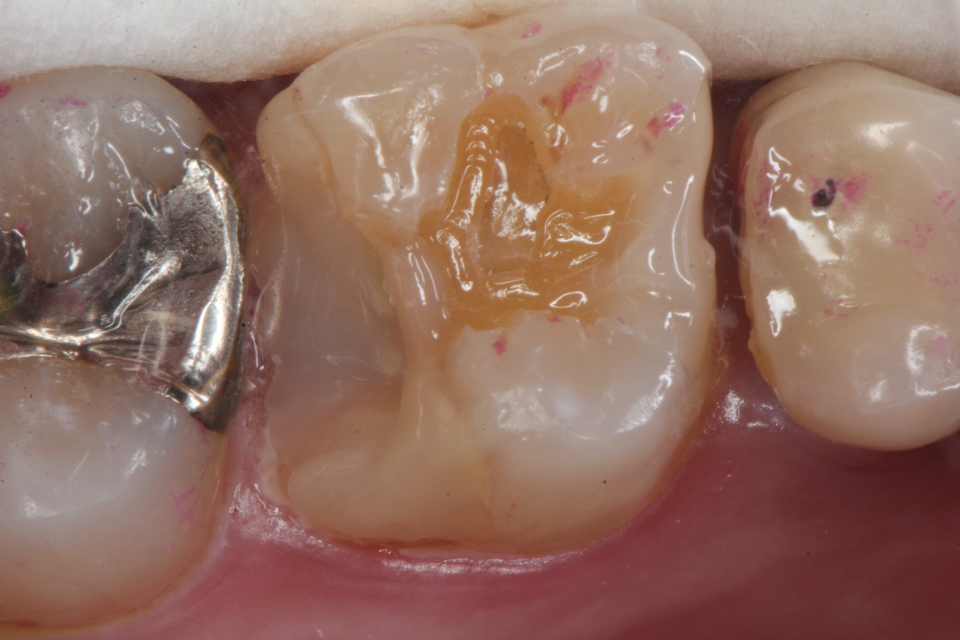

残根上のCR(ダイレクトボンディング)8 2025.11.12

ブリッジ脱離で2次カリエス+Perでグラグ… 2025.11.01

ブリッジ脱離で2次カリエス+Perでグラグ… 2025.10.31